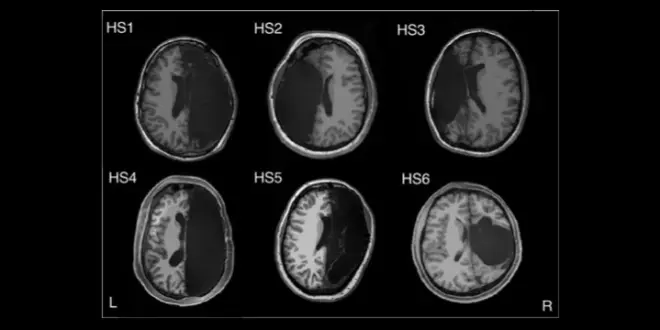

Images des six cerveaux ayant subi une hémisphérectomie.

Images des six cerveaux ayant subi une hémisphérectomie.  —  Crédits Photo : © Caltech / Kliemann et al. 2019, Cell Reports

Les chercheurs ont appuyé leur étude sur six personnes à qui des chirurgiens avaient retiré un hémisphère cérébral pour maîtriser des formes intraitables d’épilepsie lorsqu’ils étaient âgés de trois mois à 11 ans. Les scientifiques de l’institut Caltech ont ensuite réalisé des scans cérébraux sur ces sujets et les ont comparé aux images obtenues sur des personnes possédant toujours leurs deux hémisphères.